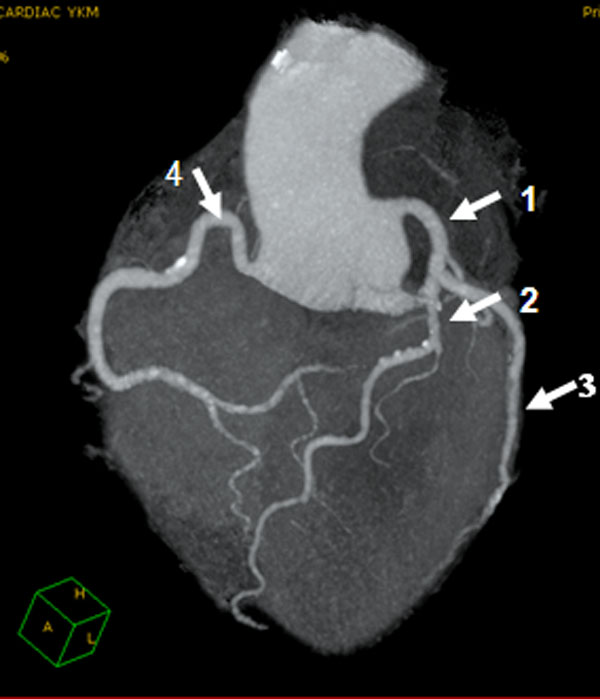

Les artères coronaires ou « coronaires » sont au nombre de deux (figure 5), la gauche et la droite. Elles naissent de l’aorte thoracique ascendante, quelques centimètres au-dessus de l’anneau aortique. Dans la distribution la plus habituelle on observe les données suivantes :

La dominance coronaire, correspondant au territoire vasculaire myocardique le plus développé, peut être gauche (la plus habituelle, décrite ci dessus) ou droite et varier d’un sujet à l’autre.

La distribution du sang au myocarde, par les branches de ramification des artères coronaires est dite de type terminal. Ceci signifie que chaque branche artérielle vascularise de manière très prédominante son propre territoire, les collatérales qui existent entre les branches artérielles n’étant habituellement pas assez développées pour assurer une éventuelle circulation de suppléance.